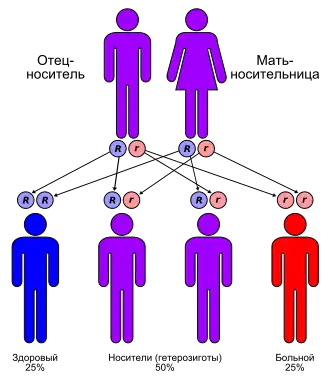

Метахроматическая лейкодистрофия наследуется, как и подавляющее большинство лизосомных болезней накопления, по аутосомно-рецессивному типу наследования[1]. Следовательно, с одинаковой частотой встречается как у мужчин, так и у женщин.

Аутосомно-рецессивный тип наследования на практике означает, что дефектный ген расположен на одной из двух аллельных аутосом. Заболевание клинически манифестирует только в случае, когда обе аутосомы, полученные по одной от отца и матери, являются дефектными по данному гену. Как и во всех случаях аутосомно-рецессивного наследования, если оба родителя несут дефектный ген, то вероятность наследования болезни у потомства составляет 1 из 4. Таким образом в среднем, на одного больного ребёнка в такой семье приходится три без клинических признаков проявлений генной болезни. На схеме синим цветом обозначены здоровые, фиолетовым — носители дефектного гена, красным — метахроматическая лейкодистрофия (два дефектных гена одной аллели). Синим кружочком помечен нормальный ген, красным — дефектный.